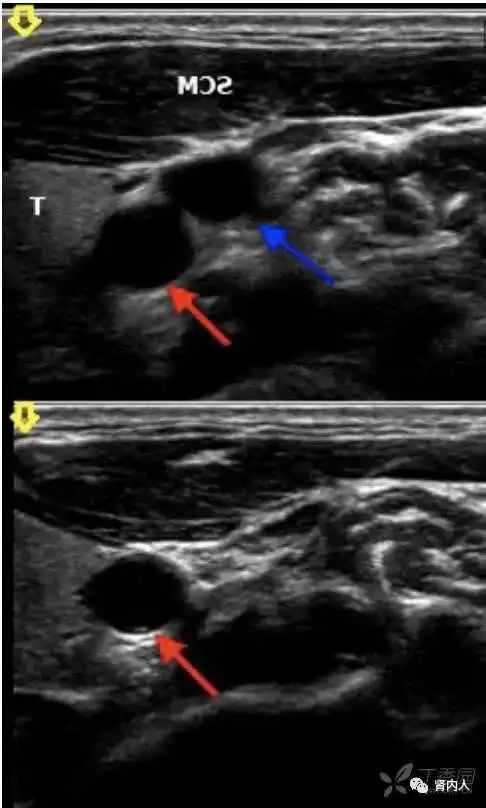

确定穿刺点,皮肤位置。

细节一:穿刺角度和深度

5ml空针钢针的长度约为3cm,与其针筒4ml的刻度相当,1.5cm的长度对应是2ml处。

细节二:手指固定与针尖斜面